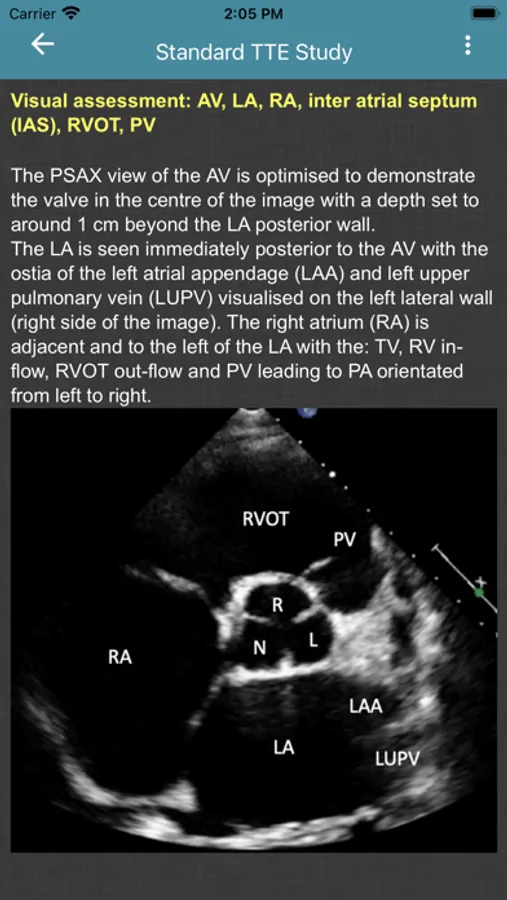

- Standard TTE Study

Screenshot 1Screenshot 2Screenshot 3Screenshot 4Screenshot 5Screenshot 6Screenshot 7Screenshot 8Screenshot 9Screenshot 10